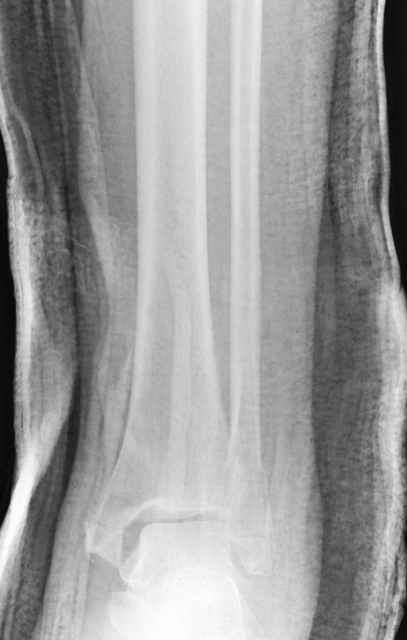

Традиционная техники АО, открытая, с точной репозицией суставной поверхности и жесткой фиксацией, из-за серёзных осложнений, которые

заканчивались ампутацией, уходит в прошлое.

Техника сегодня более щадящая, временные несложные аппараты наружной фиксации: Spanning 2 pin ExFix, Traveling traction для лигаментотаксиса, иначе сокращенные мягкие ткани невозможно восстановить позже.

Дистракция в аппарате или на вытяжение результат - лигаментотаксис, посмотреть бы, как сегодня расположены отломки.